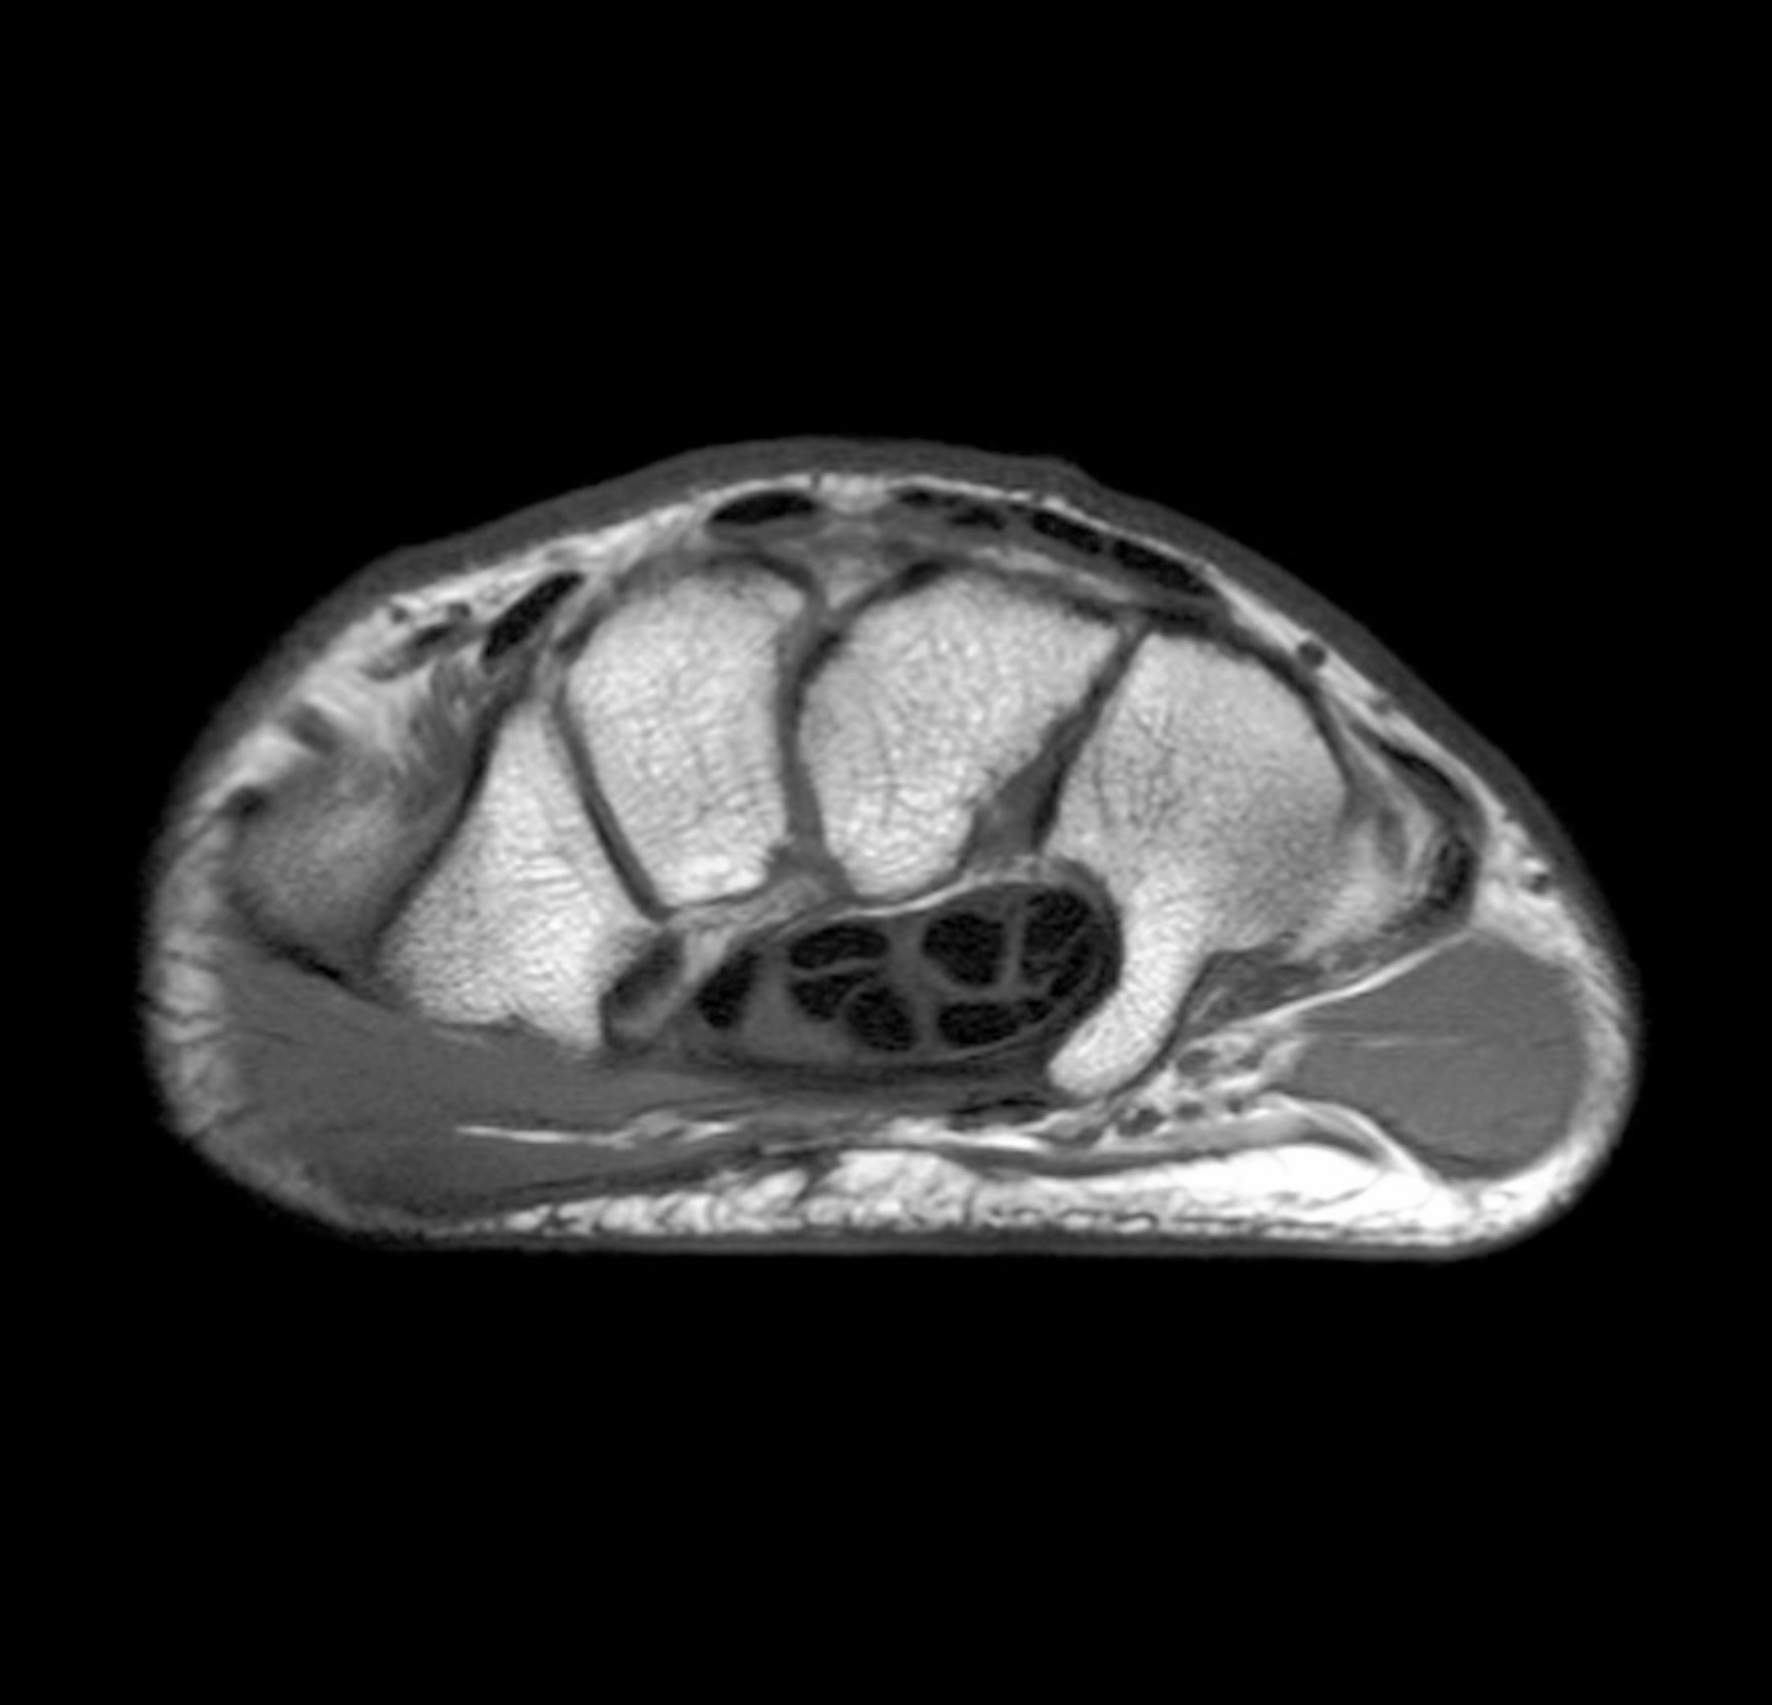

1. A 54-yr-old woman presents with atrophy of the thenar eminence and a lack of sensation on the palmar surface of the radial 3.5 digits. Testing confirms carpal tunnel syndrome with a positive Phalen’s test and Tinel’s test. Describe the boundaries and contents of the carpal tunnel. In your answer, be sure to include the function and innervation of the muscles whose tendons pass through the carpal tunnel. (G. Francis)